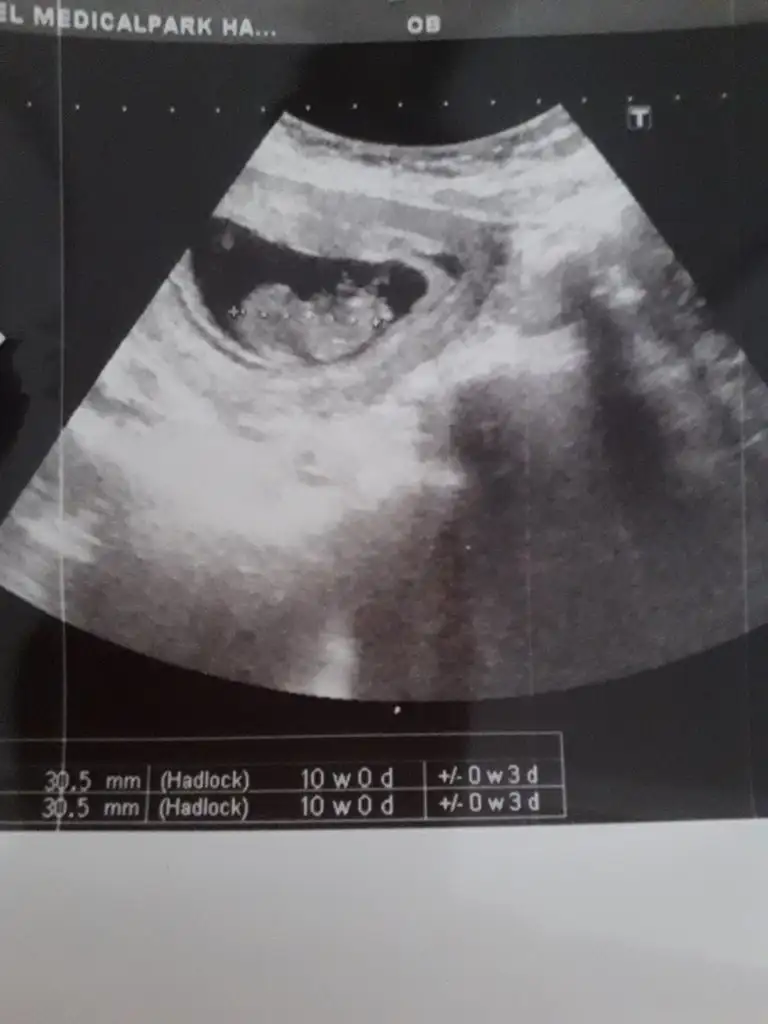

Bir kaç gün önce gittim 3 hafta sonra gel dedi canımEvet biliyorum ilkte erkrek demiştim kese konumu pek guven vermiyor o nedenle 11 12 13 hafta usg olursa paylalın 10 haftada değilde 11 haftada gitsenizsorun olurmuki dr unmu sık sık çagırıyor acaba

Mrb 13 haftalik olduk cok sukurKız gibi net de değil kız sanki 12-13 olunca tekrar usg paylaşın

Kız gibiMrb 13 haftalik olduk cok sukur

Nub için 11 12 13 hafta olmalıBir oglumuz var bir kızımız olsun cok istiyoruz tabiki öncelik sağlık

Kız gibi

bu da diger acidan fotografi ayagi kapatmis gibi amabu bu haftaki goruntusu 12. hafta gecen hafta erkek demistiniz ama emin olamamistiniz@ikrameyra